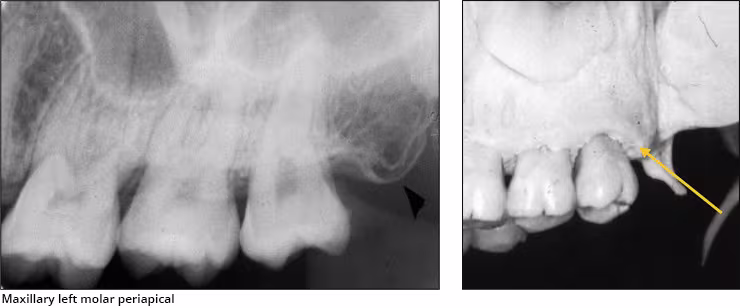

Maxillary sinus – The maxillary sinus is one of the paired paranasal sinuses. This prominent radiolucent air-filled cavity is located above the posterior teeth on the right and left sides of the maxilla. The sinus cavities are horizontally oblong bilateral structures with fine radiopaque borders. The maxillary sinus may contain septa which appear as radiopaque lines within the body of the sinus cavity. The size of the maxillary sinus can be quite variable and sometimes encroaches into the alveolar process, especially when posterior teeth are missing. Typically, the sinus appears uniform right to left. The maxillary sinus is sometimes referred to as the maxillary antrum and can be observed on both maxillary premolar and molar periapical images and partially on lateral-canine periapical images.

Maxillary tuberosity – The maxillary tuberosity is the rounded end of the alveolar process of the maxilla. This radiopaque structure appears bilaterally on maxillary molar periapical images and often on maxillary premolar periapical images and molar bitewings. The tuberosity curves upward at the end of the maxillary alveolar process. The tuberosity gives a smile appearance to the maxilla and the dentition particularly on bitewings.